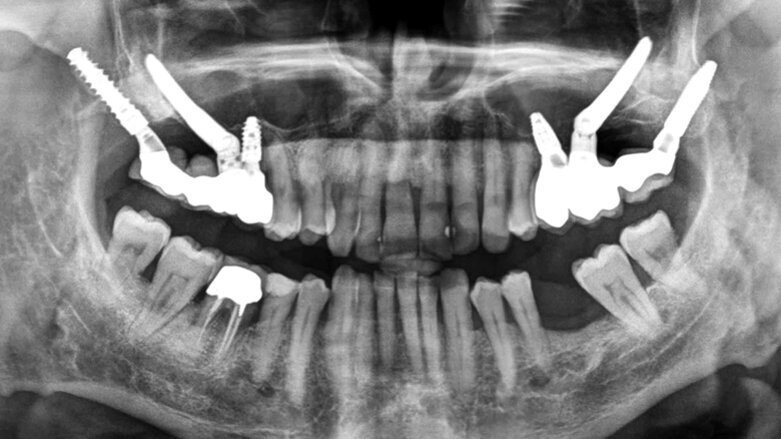

Kontrolní RTG: léčba byla v tomto případě dokončena v 5 měsících.

Muž, 56 let se k nám dostavil k rehabilitaci jeho částečně bezzubé levé horní čelisti, stěžoval si na neefektivní žvýkání. Zuby 26 a 27 byly extrahovány a nebyly nahrazeny a zuby 24 a 28 byly viklavé. Zub 25 byl endodonticky ošetřen, ale s periapikálním nálezem. Tyto 3 zuby byly přetíženy se značnou resorpcí kosti a jejich prognóza byla beznadějná. Generalizovaná parodontitis byla stabilizovaná (obr. 1). Jako náhrada zubů 24 a 25 byly zavedeny dva cylindrické samozaváděcí implantáty (Brånemark System Mk IV TiUnite regular platform [RP], Nobel Biocare) v délce 10 a 15 mm a v průměru 4 mm a následně i 35 mm dlouhý zygomatický implantát do pozice 26. Provizorní nefunkční šroubovaná fixní částečná náhrada byla okamžitě spojena se všemi třemi implantáty díky dostatečnému zaváděcímu kroutivému momentu. Pro tuto šroubovanou fixní částečnou náhradu byly použity multi-unit abutmenty (MUA, Nobel Biocare) 3 mm 17°, 2 mm 17° a 3 mm rovný RP. Finální fixní částečná náhrada byla nasazena po 4 měsících hojení (obr. 2–6).